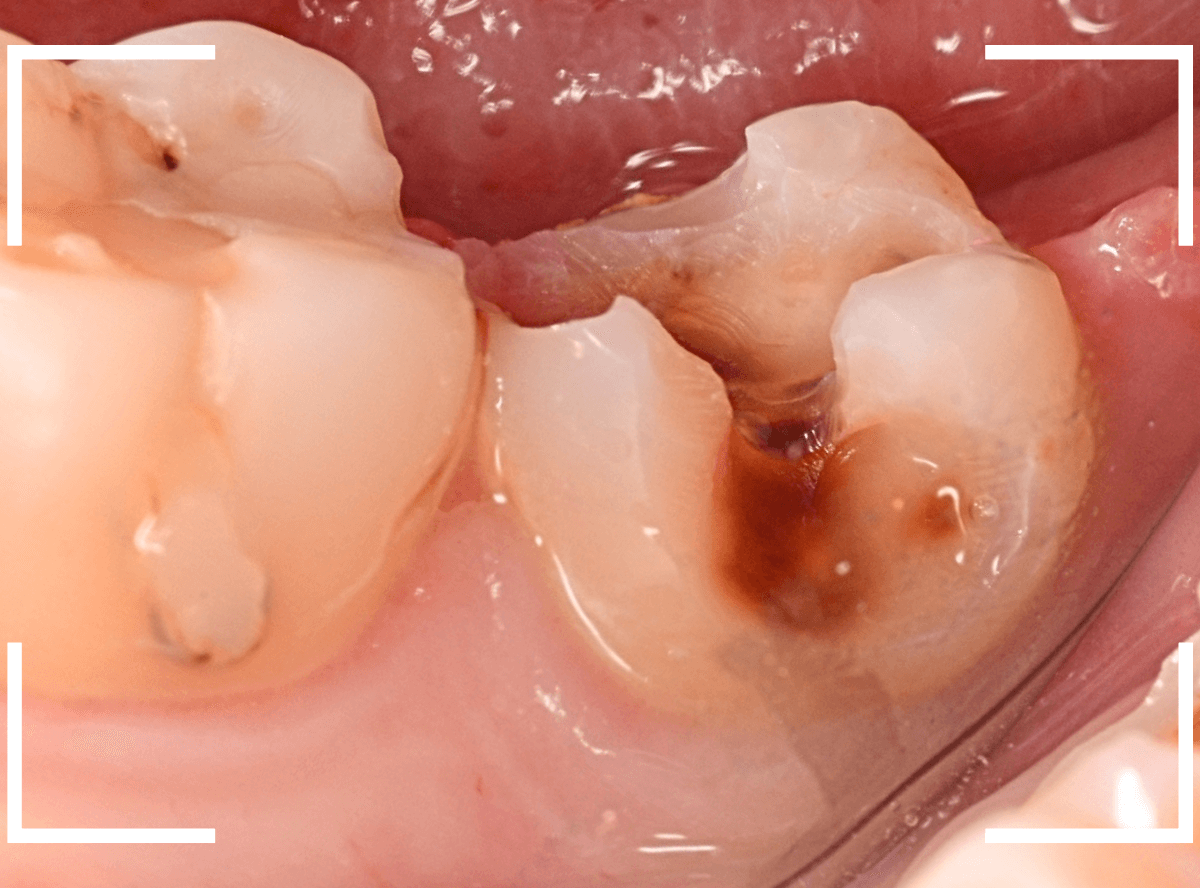

Case.9 レントゲン写真で写らない側面の虫歯

歯の側面が大きな虫歯になってしまった患者さんのケースです。

このように歯の側面が虫歯になった場合、レントゲン写真で虫歯の状況がはっきりわからない事が多いです。

レントゲン写真では、あまり大きな虫歯のようには見えません。

治療を開始します。

歯を少し削ると、すぐに大きな虫歯の穴が出てきました。

さらに虫歯を削ります。

神経に触れてしまいそうなほど、深くて広い虫歯ですね。

全ての虫歯を除去したところです。

何とか神経に触れる寸前のところで踏みとどまれましたが、レントゲン写真からは想像できない虫歯の深さでした。

繰り返しになりますが、虫歯の治療も奥が深く、長年歯科治療をしている我々でも診断に苦慮する場合があります。

くれぐれも、自己判断はせずに、定期メンテナンスに来てくださいね。